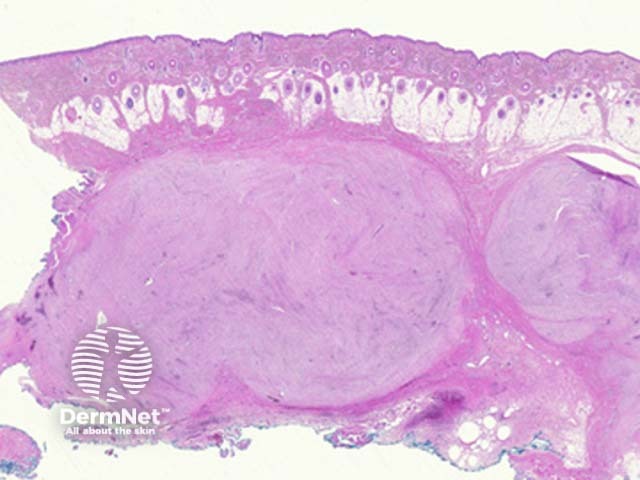

Low power examination of nodular fasciitis shows a well-circumscribed discrete mass in the subcutaneous adipose tissue (figure 1). Dermal and intravascular forms have also been described.

Figure 1